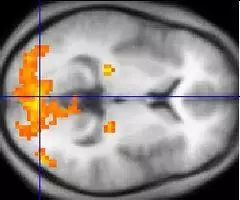

Functional neuroimaging is the use of neuroimaging technology to measure an aspect of brain function, often with a view to understanding the relationship between activity in certain brain areas and specific mental functions. It is primarily used as a research tool in cognitive neuroscience, cognitive psychology, neuropsychology, and social neuroscience.

PET, fMRI, fNIRS and fUS can measure localized changes in cerebral blood flow related to neural activity. These changes are referred to as activations. Regions of the brain which are activated when a subject performs a particular task may play a role in the neural computations which contribute to the behaviour. For instance, widespread activation of the occipital lobe is typically seen in tasks which involve visual stimulation (compared with tasks that do not). This part of the brain receives signals from the retina and is believed to play a role in visual perception.

Traditional "activation studies" focus on determining distributed patterns of brain activity associated with specific tasks. However, scientists are able to more thoroughly understand brain function by studying the interaction of distinct brain regions, as a great deal of neural processing is performed by an integrated network of several regions of the brain. An active area of neuroimaging research involves examining the functional connectivity of spatially remote brain regions. Functional connectivity analyses allow the characterization of interregional neural interactions during particular cognitive or motor tasks or merely from spontaneous activity during rest. FMRI and PET enable creation of functional connectivity maps of distinct spatial distributions of temporally correlated brain regions called functional networks. Several studies using neuroimaging techniques have also established that posterior visual areas in blind individuals may be active during the performance of nonvisual tasks such as Braille reading, memory retrieval, and auditory localization as well as other auditory functions.[2]

Functional neuroimaging studies have to be carefully designed and interpreted with care. Statistical analysis (often using a technique called statistical parametric mapping) is often needed so that the different sources of activation within the brain can be distinguished from one another. This can be particularly challenging when considering processes which are difficult to conceptualise or have no easily definable task associated with them (for example belief and consciousness).